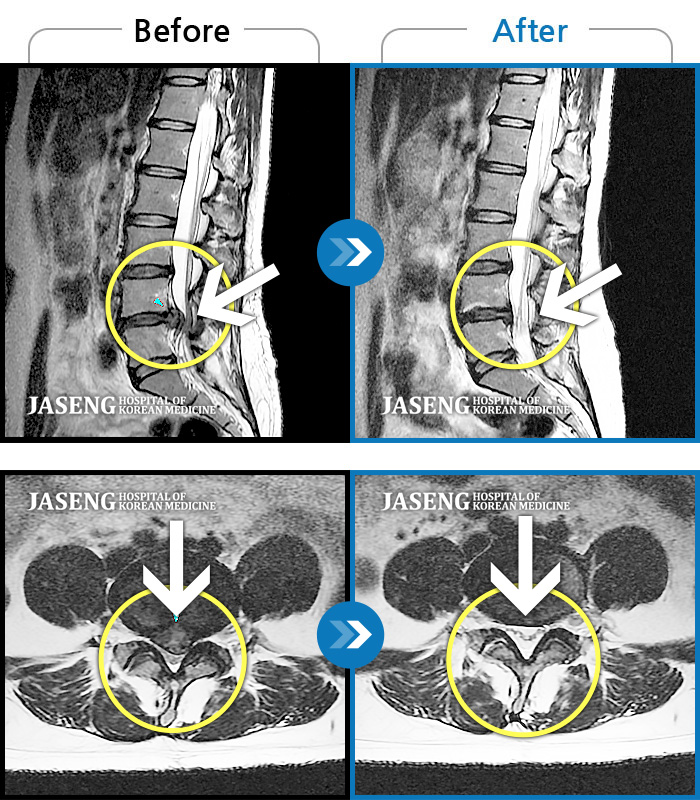

허리디스크

보라매 · 왕오호 원장

허리와 좌측 엉치 통증

촬영시기

2015.12.29 ~ 2018.10.11

2018.12.28

조회수 3,338